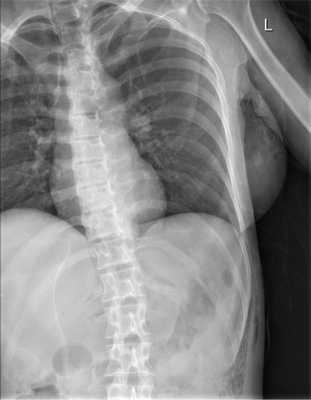

Больная М., 48 лет, поступила в приемное отделение НИИ СП им. Н.В. Склифосовского с жалобами на боль в левой половине живота, общую слабость, на 2-е сутки с момента получения травмы (удар копытом лошади в живот). При осмотре отмечены болезненность при пальпации грудной клетки слева, в левых отделах живота, развитие подкожной эмфиземы грудной клетки.

При рентгенологическом исследовании органов грудной клетки и брюшной полости (рис. 1) Рис. 1. Рентгенограмма органов грудной клетки и брюшной полости больной М. при поступлении. выявлена подкожная эмфизема слева от переднего отрезка VI ребра с переходом на брюшную полость. При УЗИ в 5 областях брюшной полости определяется свободная жидкость.